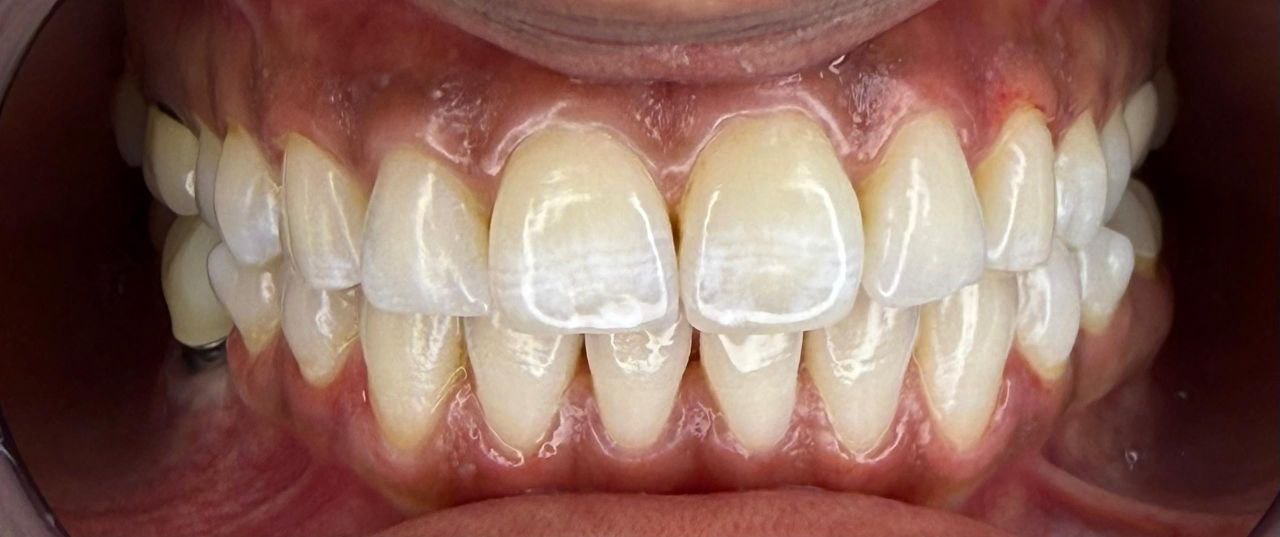

قبل و بعد لیمینت

قبل و بعد لیمینت

قبل و بعد لیمینت

قبل و بعد لیمینت